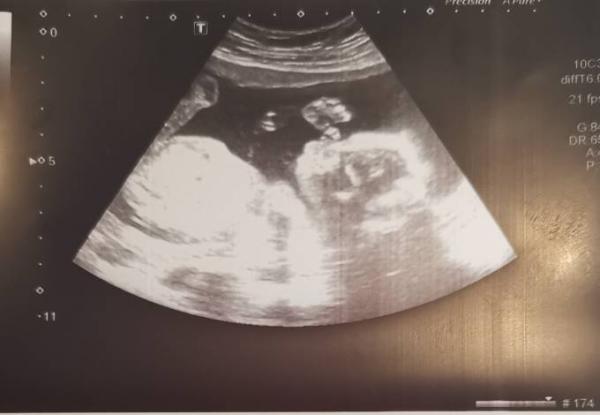

Hallo ihr lieben Ich hatte heute bei 17+5 meinen zweiten großen Ultraschalltermin. Nach der Tendenz bei der Nackenfaltenmessung hat es sich jetzt (absolut eindeutig ) bestätigt - wir sind wieder Team blau Ich freu mich total über unseren zweiten Sohn. Die Ärztin und ich mussten so lachen. Der kleine lag im Bauch und hat mit seinem Penis gespielt. Sie hat gemeint das hat sie auch noch nie gesehen Sonst ist alles gut und gesund. Ich hab leider eine Infektion die mit Antibiotika behandelt werden muss aber sonst passt alles. Anbei noch ein ganz tolles Bild von heute

Bild zu Outing 💞 - Forum für Juni - Mamis